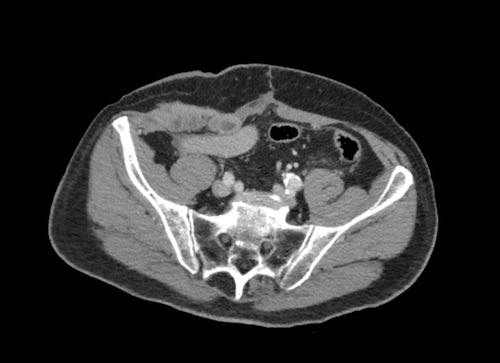

Ca lâm sàng 2

Cuộn qua các lát cắt.

Bạn có thể phát hiện tất cả các tổn thương cấy ghép phúc mạc không?

.jpeg)